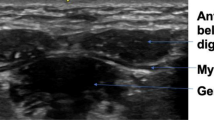

For the lateral pterygoid muscle, the transducer was placed along the zygomatic arch then relocated caudally to the mandibular notch in the horizontal plane, where a hypoechoic gap can be identified between the coronoid and condylar processes of the mandible20. After opening the mouth, the lateral pterygoid muscle was fully observed as a triangular-shaped muscle attached to the lateral pterygoid plate (Fig. 4). The distance between the outer and inner fasciae in the middle of the lateral pterygoid muscle was defined as its thickness. The scanning protocol of the three muscles was summarized in supplementary Table 1.

Ultrasound imaging (A) when the transducer is placed in the horizontal plane caudal to the zygomatic arch with the mouth closed (B). Ultrasound imaging (C) of the lateral pterygoid muscle (LPM) when the transducer is placed in the horizontal plane caudal to the zygomatic arch with the mouth opened (D). The length of the dashed lines indicates the thickness of the muscle. MM, masseter muscle; CORP, coronoid process; CODP, condylar process; TM, temporalis muscle; LPM, lateral pterygoid muscle.